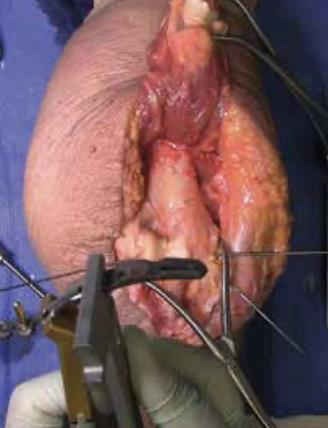

• Plate selection

• Select the first plate (medial or lateral).

• If necessary, contour to optimize fit using bending instruments.

• If using bending pliers, a Locking Cap can be applied temporarily to prevent deformation of the distal hole.

• Shaft fixation

• Position the plate such that the epicondylar screw hole (2nd node on the plate) is located on the apex of the epicondyle.

• First, fix the plate to the proximal fragment.

• Using the HPS Drill Guide, drill through the chosen FreeFix® slot using the 2.7mm x 50mm Drill Bit.

• Using the FreeFix® scale of the depth gauge, measure then insert a 3.5mm compression screw (FreeFix® Compression) for fixation to the humeral shaft.

• Distal fragment fixatiion

• Provisionally secure the articular portion to the shaft by inserting, through the Epicondylar Node, a 2.7mm provisional Smooth Peg or a 2.0mm K-Wire as follows

• If a 3.5mm Metaphyseal Screws will be later used for final fixation, use a 2.7mm Drill Bit to drill through the Epicondylar Holes and insert the Smooth Pegs with the T-10 Driver.

• If using 2.7mm Metaphyseal Screws for final fixation, insert the 2.0mm AIMing Guide into the pre-loaded Drill Guide and drill through the Epicondyle with a 2.0mm K-Wire.

• Repeat for the second plate

• TiBeam® canal preparation

• Use the Trajectory Guide to insert the 1.5mm x 229mm K-Wire through the most distal holes of the medial and lateral plates via the Bushing Sleeve.

• Measure length using marks on the Bushing Sleeve or a standard Depth Gauge (from plate to plate).